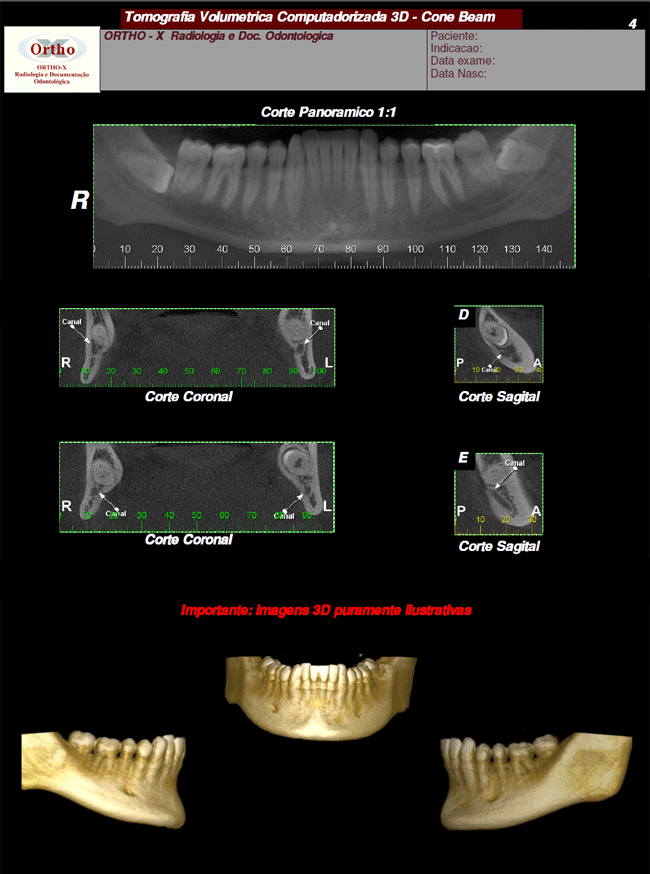

Exames > Tomografia Computadorizada 3D > Exemplo de Exames: Localização de Canal

Exemplo de Exames: Localização de Canal